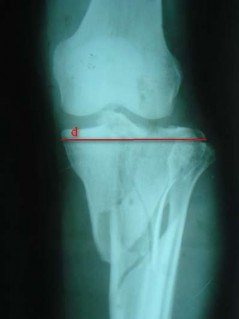

Độ tăng bề rộng mâm chày được xác định theo các bước:

- Đo kích thước ngang lớn nhất của mâm chày ở chân gãy (khoảng cách d trong Hình 2.13) và chân không gãy (d’).

- Độ tăng bề rộng mâm chày là hiệu số của d – d’.

Hình 2.13. Cách xác định bề rộng mâm chày ở chân gãy.